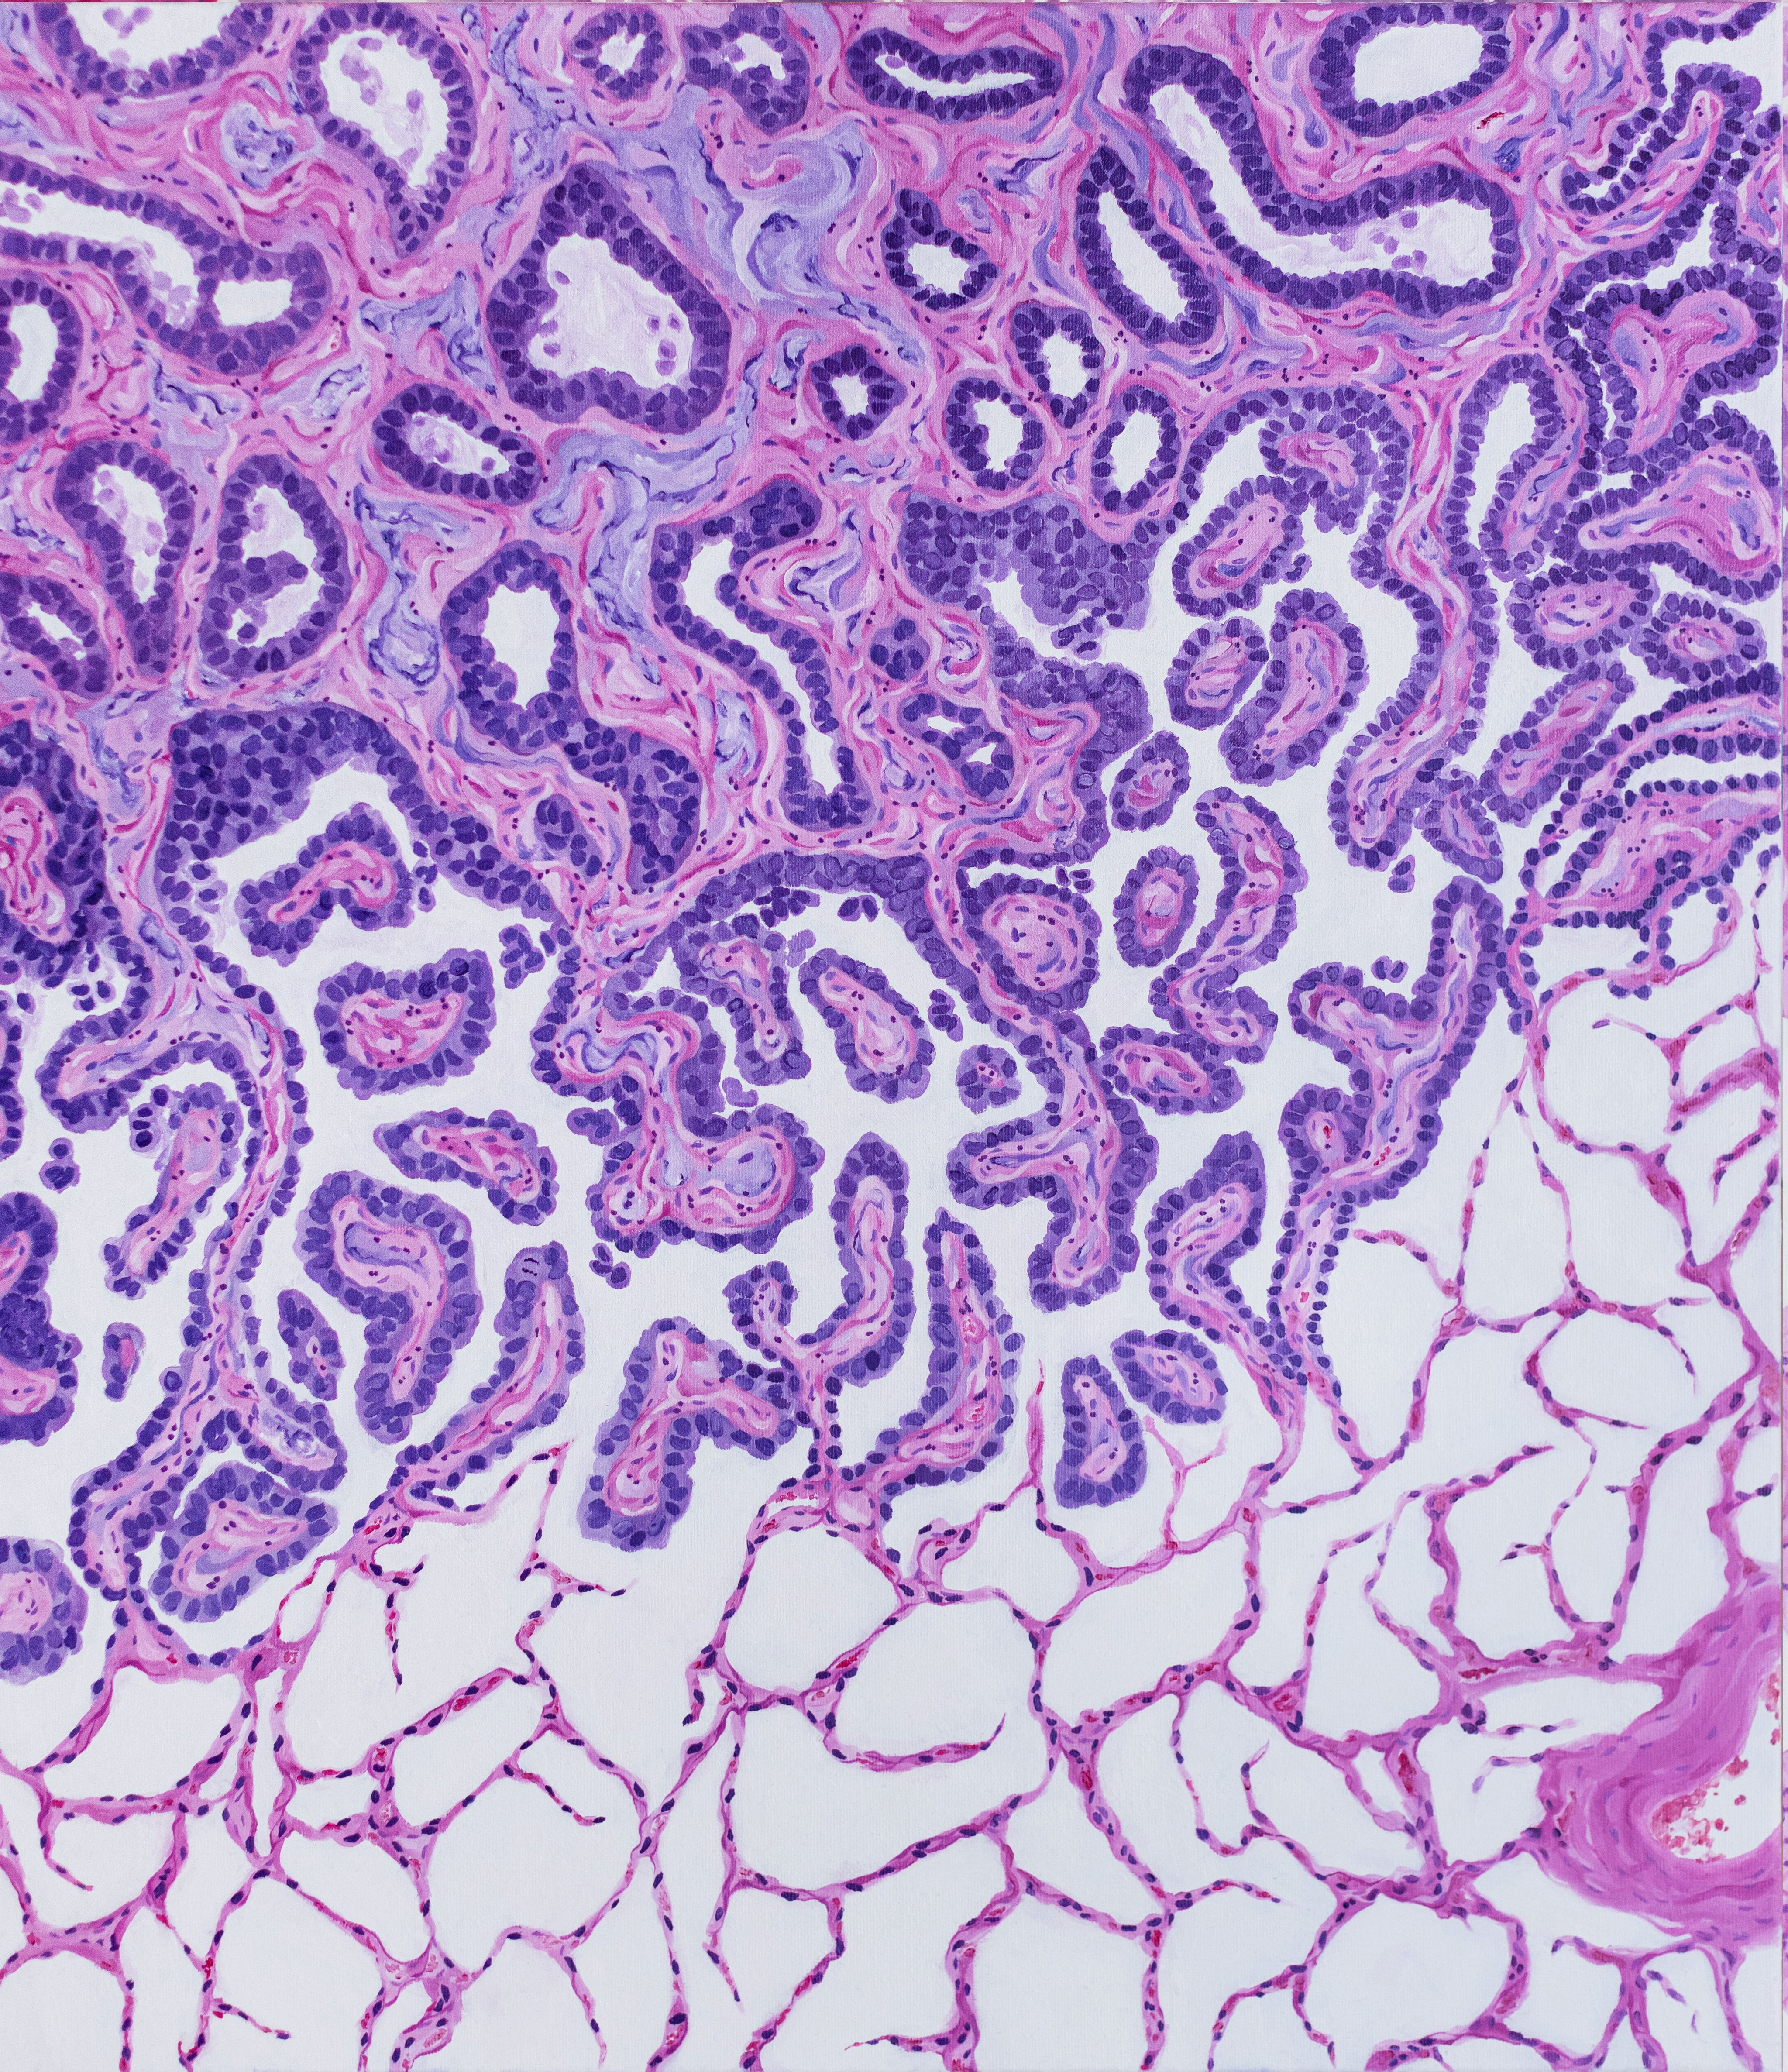

Gastrointestinal Flowers by Aneta Vareškić, Molecular Biologist (Genetics) at the University Clinical Center Tuzla, Bosnia and Herzegovina and Ivana Čerkez, Pathology Resident at the University Clinical Center Tuzla, Bosnia and Herzegovina. This artwork is inspired by normal colonic histology, emphasizing the organized glandular architecture and epithelial integrity that form the basis of gastrointestinal health and effective interaction with dietary and environmental factors.